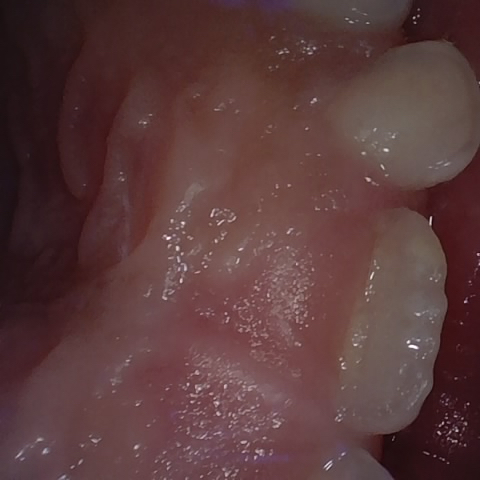

Annotated as "Good"